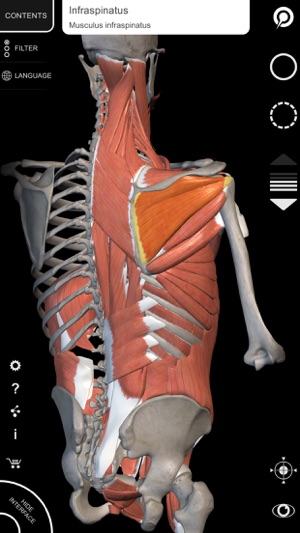

"Muscle | Skeleton" is a useful tool for students of medicine and physical education, for physicians, orthopedists, physiatrists, physiotherapists, kinesiologists, paramedics, nurses and athletic trainers.

• Rotate and Zoom every model in the 3D space

• Intelligent rotation, automatically moves the centre of rotation for easier navigation

• Muscles descriptions (origin, insertion, innervation, action), in english